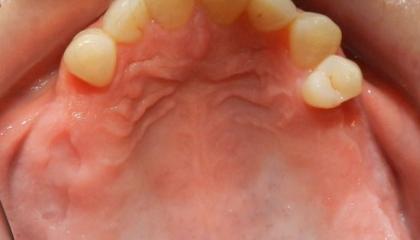

Before